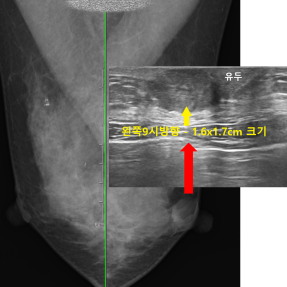

Skin Lump Clinic

피부혹 클리닉